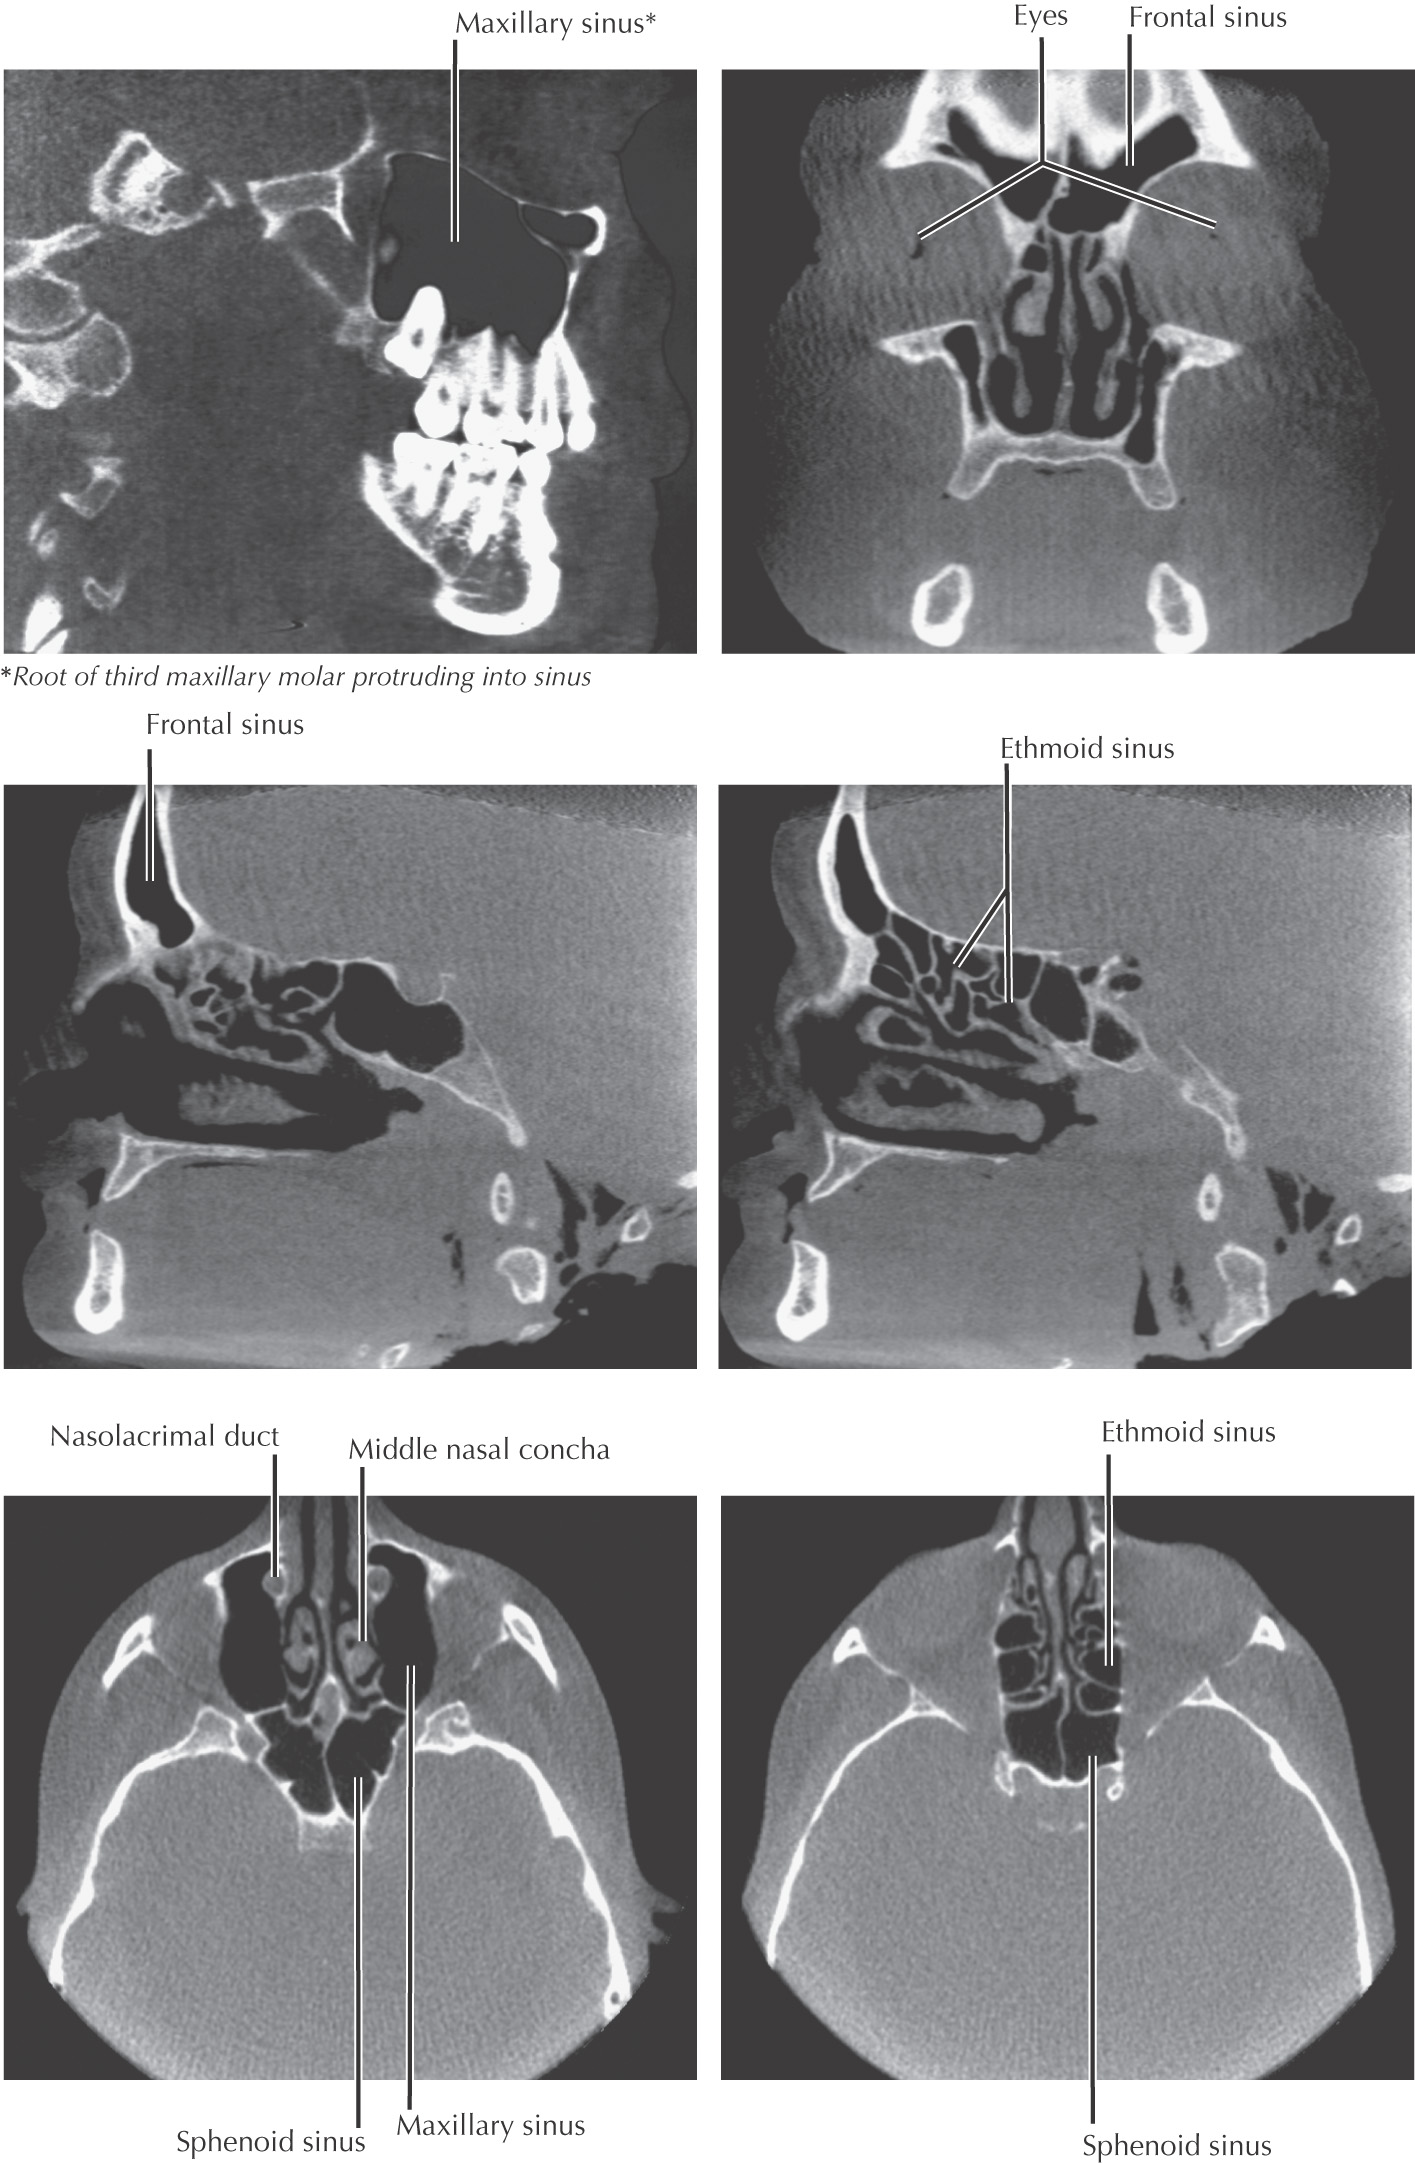

Paranasal sinuses: invaginations from the nasal cavity that drain into spaces associated with the lateral nasal wall

All paranasal sinuses drain into the nasal cavity

May find 3 to 18 ethmoid air cells on each side

Large pyramidal cavity

Two large, irregularly shaped cavities